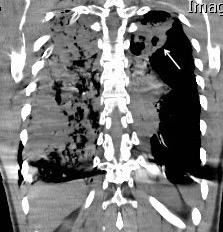

Signos radiológicos TC

Hallifax RJ et al. State-of-the-art: Radiological investigation of pleural disease Respiratory Medicine 2017

Nivel hidroaéreo o burbujas

Forma lenticular o elíptica Ángulos obtusos

> Grasa Extrapleural (60-80%)

Situación no gravitacional (no siempre)

Compresión de estructuras pulmonares

Límite muy bien definido Tabicación

Engrosamiento de la pleura parietal 36/ 59 exudados (61%) 56% de D. paraneumónicos 100% de empiemas Especificidad.. 96%.

Exudado versus trasudado.

Aquino SL, et al. Pleural exudates and transudates: diagnosis with contrast-enhanced CT. Radiology 1994